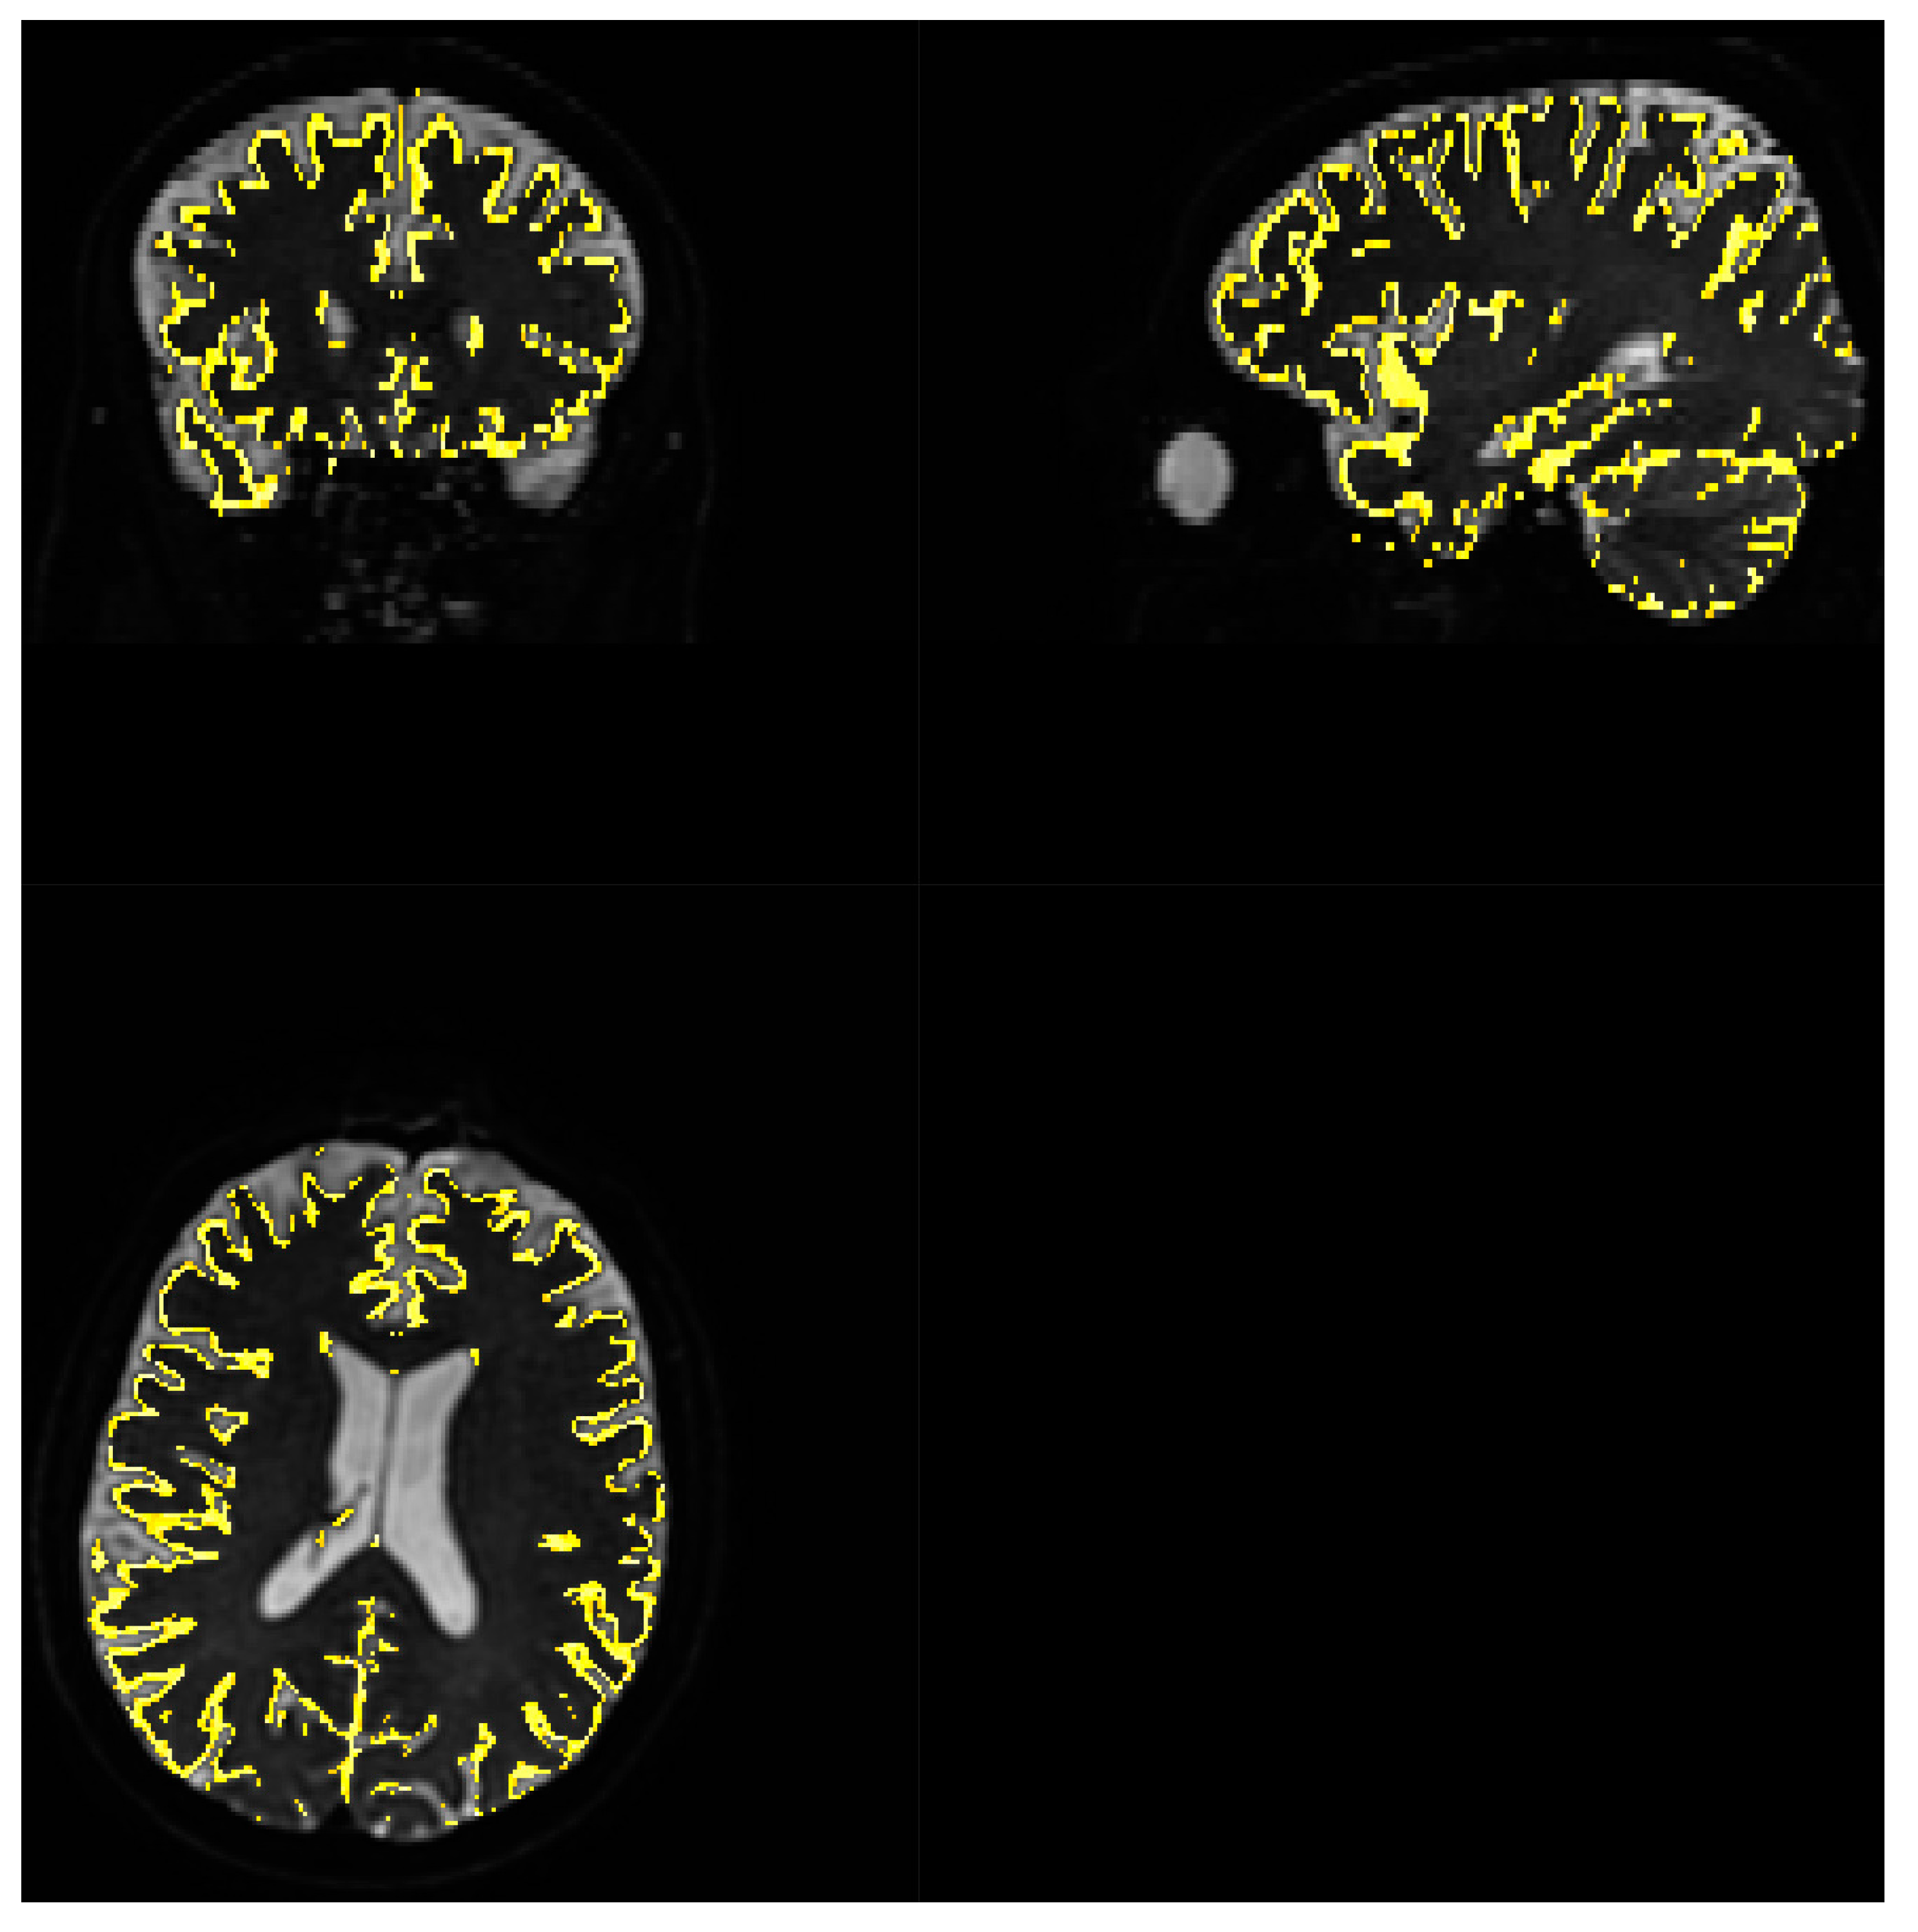

Figure 3. Gray matter coverage on DWI scan. Yellow shape represents the coverage of gray matter map with probability >80% overlayed on b 0 image, regridded to IVIM DWI resolution.

FSL FMRIB’s Automated Segmentation Tool was used on T1 and T2 image to create white matter and gray matter maps. As T1 and IVIM MRI were acquired as first and last imaging sequence respectively, thus coregistration of T1 to b 0 IVIM scan was necessary because of discrepancies in spatial alignment caused by patient movement. This coregistration was performed using SPM12 [27] using Normalized Mutual Information objective function. Similarly to the above IVIM parameter estimations for white matter and grey matter were computed based on the averaged signal from the region after normalizing each voxel to its maximal value.

SNR level was estimated for white matter and grey matter voxels separately, with use of FSL FAST segmentation with Tissue Probability Maps (TPM). Acquiring high resolution T2 data allowed for high precision separation of these two tissue types. The results were comparable to whole brain analysis and each other. Estimated parameters for white matter, based on 210523 voxels were as follows: a v e r a g e = 21.56 ,     m e d i a n = 21.23 ,     m i n i m u m = 1.36 ,   m a x i m u m = 62.14   . For grey matter, based on 68067 voxels a v e r a g e = 20.69 ,     m e d i a n = 20.32 ,     m i n i m u m = 1.25 ,   maximum = 117.77 .